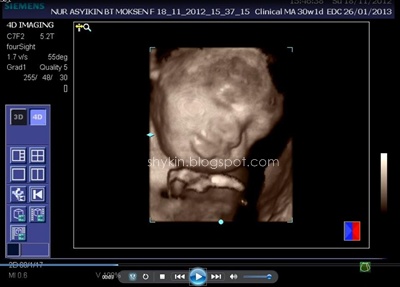

Alhamdulillah masa aku menaip entry ni usia kandungan dah masuk 31 minggu. Bermaknanya kurang dari 10 minggu aku akan melahirkan. Ops lupa nak bagitahu yang EDD aku kali ini ialah pada 26 JAN 2013. Yes! tambah lagi sorang anak januari dalam keluarga aku selain dari Fathi. So, dah tau dah pasni kalau sambut birthday boleh buat serentak dengan Fathi punya sebab dia lahir pada 15hb Januari. (* Jimat )

Dulu masa pregnant Fayyadh dan Fathi scan 2D je yang aku tahu. So, Kali ni konon-konon nak merasa la scan 3D. 4D pulak, aku pun ajak la suami pergi buat dekat klinik. Memang teruja la sebab 4D bole dengar sound dan tengok dia gerak-gerak dengan gambar coklat tu. Dah macam ada kat depan mata je baby padahal masih lagi dalam perut. Jakun jugak la haku... ngeh ngeh ngeh.

BTW aku buat dekat Klinik Sofea, Puchong Utama, scan 3d 4d murah la kat situ, RM80 sekali dengan CD. Setakat ini aku rasa kat KL ni tu yang paling murah. Lagi pula, tak payah buat appointment, walk-in terus je.

Proses scan dijalan oleh doktor yang bertugas masa tu. Okeyla jugak, puas hati sebab dia print hampir 10 keping result scan muka tu. Banyakkan??..

Selain scan tengok muka, doktor tu bagi tahu perkembangan graf baby dalam kandungan. Doktor tu cerita la berat baby berapa, jantung dia okey ke tak, tumbesaran dia normal ke tak, air ketuban cukup ke tak, dan yang paling penting dia bagitahu dan 'tunjuk' sekali jantina baby. (* excited kan ? )

Jom view hasil 4dscannya. Yang ni aku printscreen dari VCD yang klinik tu bagi.

Ini pulak hasil 4dscan. Banyak jugak doktor tu print kan.

Insyallah, kami bakal menimang cahayamata PEREMPUAN. kalau ikut scan tula..

sebenarnya tak kisah pun jantina apa, tapi puas hati sebab dapat tahu yang dia sihat kat dalam kandungan.